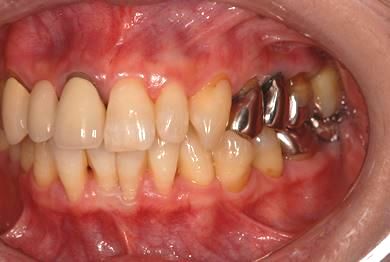

| 性別/年齢 | 女性 / 50歳 | ||||||||||||||||||||||||||||||||

| 主訴 | 銀のかぶせが取れたところと、痛みがある歯をセラミックで治療したい。 | ||||||||||||||||||||||||||||||||

| 治療内容 | メタルボンドセラミック3本(メタルボンドセラミッククラウン用土台3本) | ||||||||||||||||||||||||||||||||

| 総治療費 | 374,063円 | ||||||||||||||||||||||||||||||||

| 治療期間 | 10ヶ月 |